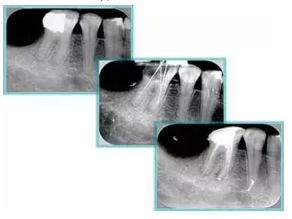

( 3 )塑化 + 根充。

如圖為塑化加根充處理后牙齒 X 線片。

二、臺階

定義:根管內(nèi)壁上人為產(chǎn)生的不規(guī)則形狀阻止器械順利進(jìn)入根尖。

原因:器械沒有預(yù)彎,根向壓力過大。

右圖箭頭處示臺階形成。